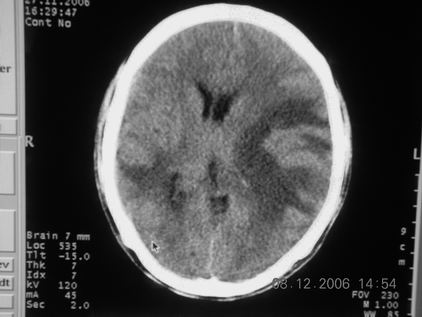

标题: CT11164:男,46岁,白血病患者,,大家看看. [打印本页]

标题: CT11164:男,46岁,白血病患者,,大家看看.

以前的片子,病史忘了,男,46岁,白血病患者,后来到中山二院诊断为

谁见过白血病中枢系统改变是怎么样的吗?

白血病脑浸润。

支持白血病脑浸润.

1 多发脑脓肿可能性大.>2 白血病浸润.

白血病脑浸润。没见过!但结合病史应首先考虑此病。

支持白血病脑浸润

结合病史考虑白血病脑浸润。

结合白血病病史,支持考虑白血病脑浸润。

结合病史考虑白血病脑浸润